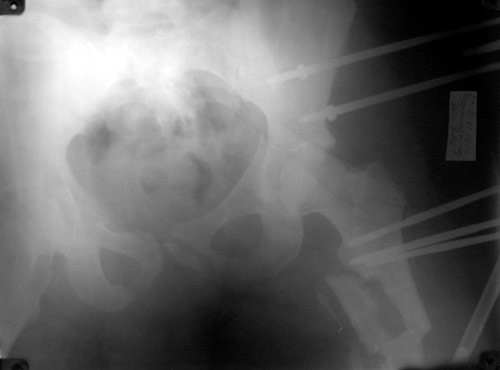

Таз

Бедро

То, что получилось в приложении. Стоит ли дальше тянуть головку винтами или низводить проксимальный отломок по оси?

Уважаемый Борис! Я не имел возможности ознакомиться с рентгенологической картиной сразу после травмы. Имею картинку на данный момент (Ваше приложение). Считаю, что Вы имеете право оставить всё в имеющемся состоянии, но желательна дополнительная дистракция по оси шейки бедренной кости. Далее стабилизировать аппарат. Артроз больному обеспечен, сроки наступления его декомпенсации известны только аллаху.

С> То, что получилось в приложении.

Можно только порадоваться за пациента и врачей, положение отломков значительно улучшилось. Может быть, удастся добиться "вторичной конгруэнтности" даже при сохраняющемся диастазе на уровне перелома. Из того, что видно - стержней в тазу маловато, лучше бы зацепиться за гребни подвздошных костей (по 3-4 стержня), тогда можно будет пациента и поднять на костыли.

С> Стоит ли дальше тянуть головку винтами или низводить проксимальный

С> отломок по оси?

Возможно, и то, и другое. По одной прямой проекции ситуацию не оценить - желательно сделать косые проекции (Judet) левой вертлужной впадины, на которых будет видно, конгруэнтна ли головка со сводом, не надо ли подвинуть ее кпереди или кзади.

По бедру - ось (по одной проекции) и длина восстановлены. Непривычно выглядит стержень с медиальной стороны, мы обычно обходимся только

наружной полуокружностью бедра. Если аппарат здесь предполагается как окончательный фиксатор - похоже, это надолго...

На первый взгляд репозиция вертлужной впадины не плохая, однако следует сделать проекционные снимки по Judet, а вот аппрат конечно подкачал, да и больного жалко. Былобы красиво сейчас после рентген-контроля перкутанно ппровести стягивающие винты через перелом вертлужной впадины из подвздошной в лобковую и из седалищной в подвздошную. А бедро заштифтовать, а потом снять аппарат и отпустить больного, передний отдел возможно фиксировать АВФ.